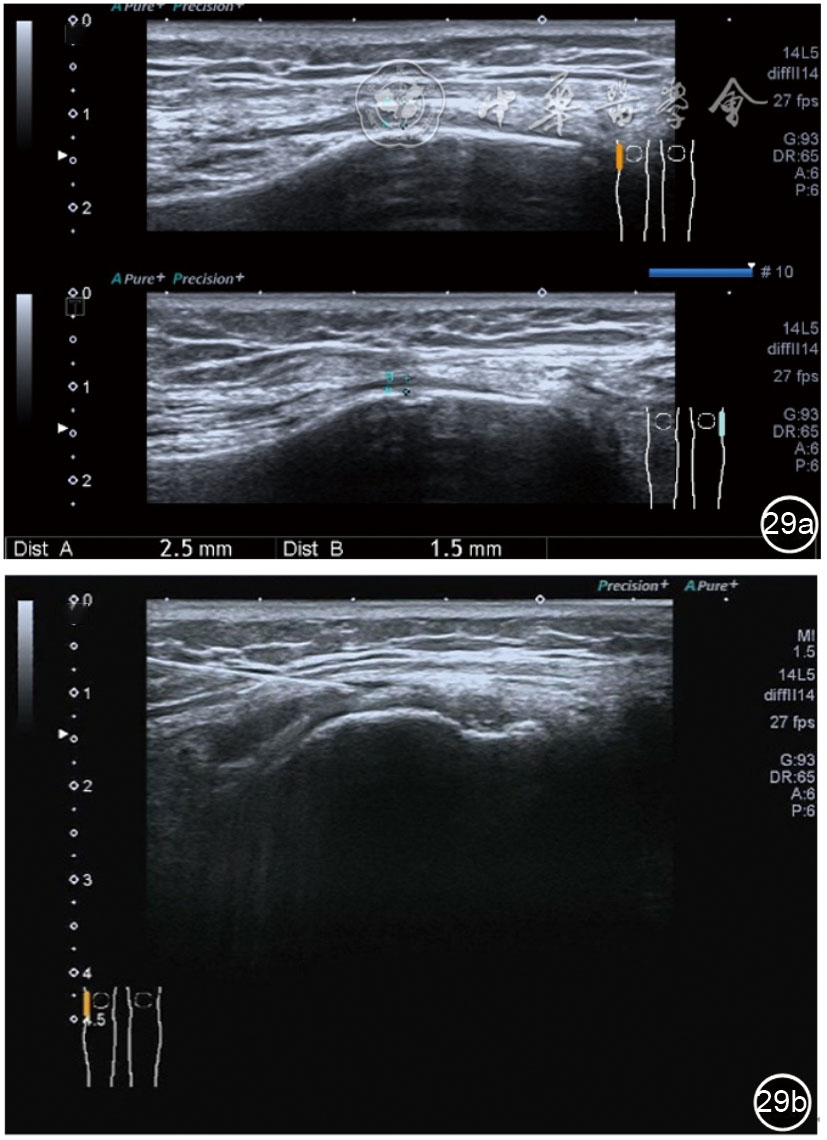

1.髂胫束局部治疗。仍以保守治疗为首选。如物理治疗、口服药物、康复训练等,早期可以超声引导下肌腱表面注射治疗。针刀剥离松解治疗具有创伤小、恢复时间短、感染率低、适应证广,无绝对禁忌证等优势,可作为首选手术方案。(1)髂胫束胫骨附着点表面局部药物注射治疗。患者侧卧位,髋内旋,膝关节屈曲20°~30°,膝下垫枕。局部消毒,铺无菌巾,穿刺区域常规消毒,探头涂抹耦合剂后套入无菌手套碘伏消毒或使用无菌耦合剂,长轴显示髂胫束,找到胫骨附着点病变部位。选用25G针头,抽取1%利多卡因3 ml+曲安奈德10 mg,超声引导下针尖到达肌腱表面进行注射(图28),注射完毕拔出针头,局部压迫2分钟,穿刺点创可贴覆盖。(2)髂胫束股骨外髁附着点局部药物注射治疗。体位及治疗前准备同髂胫束胫骨附着点表面局部药物注射治疗,长轴显示髂胫束,找到股骨外髁附着点病变部位。确定髂胫束与股骨外髁之间为靶点,选用25G针头,抽取1%利多卡因3 ml+曲安奈德10 mg,超声引导下,针尖到达骨表面进行注射(图29),注射完毕拔出针头,局部压迫2分钟,穿刺点创可贴覆盖。(3)髂胫束胫骨附着点局部针刀剥离松解治疗。体位及治疗前准备同髂胫束胫骨附着点表面局部药物注射治疗。超声探头长轴位扫查,根据压痛点和超声显示肌腱变化的位置确定靶点。用1%利多卡因3 ml沿韧带表面及胫骨止点病变部位局部麻醉。选用直径0.6 mm的Ⅰ型2号针刀由近端向远端平面内进刀,平刀在韧带表面剥离松解3~5刀,然后进入胫骨附着点损伤处进行剥离松解3~4刀拔出针刀(图30),局部压迫止血5分钟,无菌敷料覆盖。(4)髂胫束股骨外髁附着点局部针刀剥离松解治疗。体位及治疗前准备同髂胫束胫骨附着点表面局部药物注射治疗。超声探头长轴位扫查,根据压痛点和超声显示肌腱变化的位置确定靶点。用1%利多卡因3 ml沿股骨外髁部位的髂胫束表面局部麻醉。选用直径0.6 mm的Ⅰ型2号针刀由近端向远端平面内进刀,平刀在髂胫束表面剥离松解3~5刀拔出针刀(图31),局部压迫止血5分钟,无菌敷料覆盖。

图30 超声引导下髂胫束胫骨附着点局部针刀剥离松解治疗

图31 超声引导下髂胫束股骨外髁附着点局部针刀剥离松解治疗